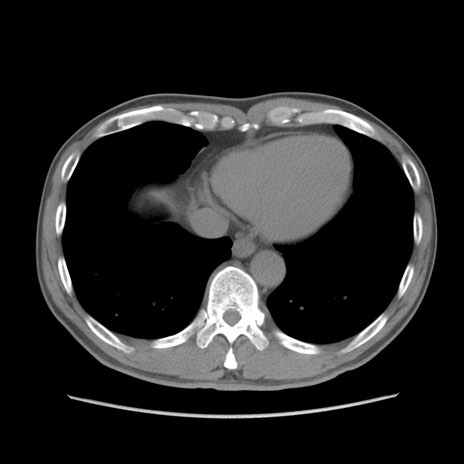

症例56 CT(横断像)

脂肪ウインドウ